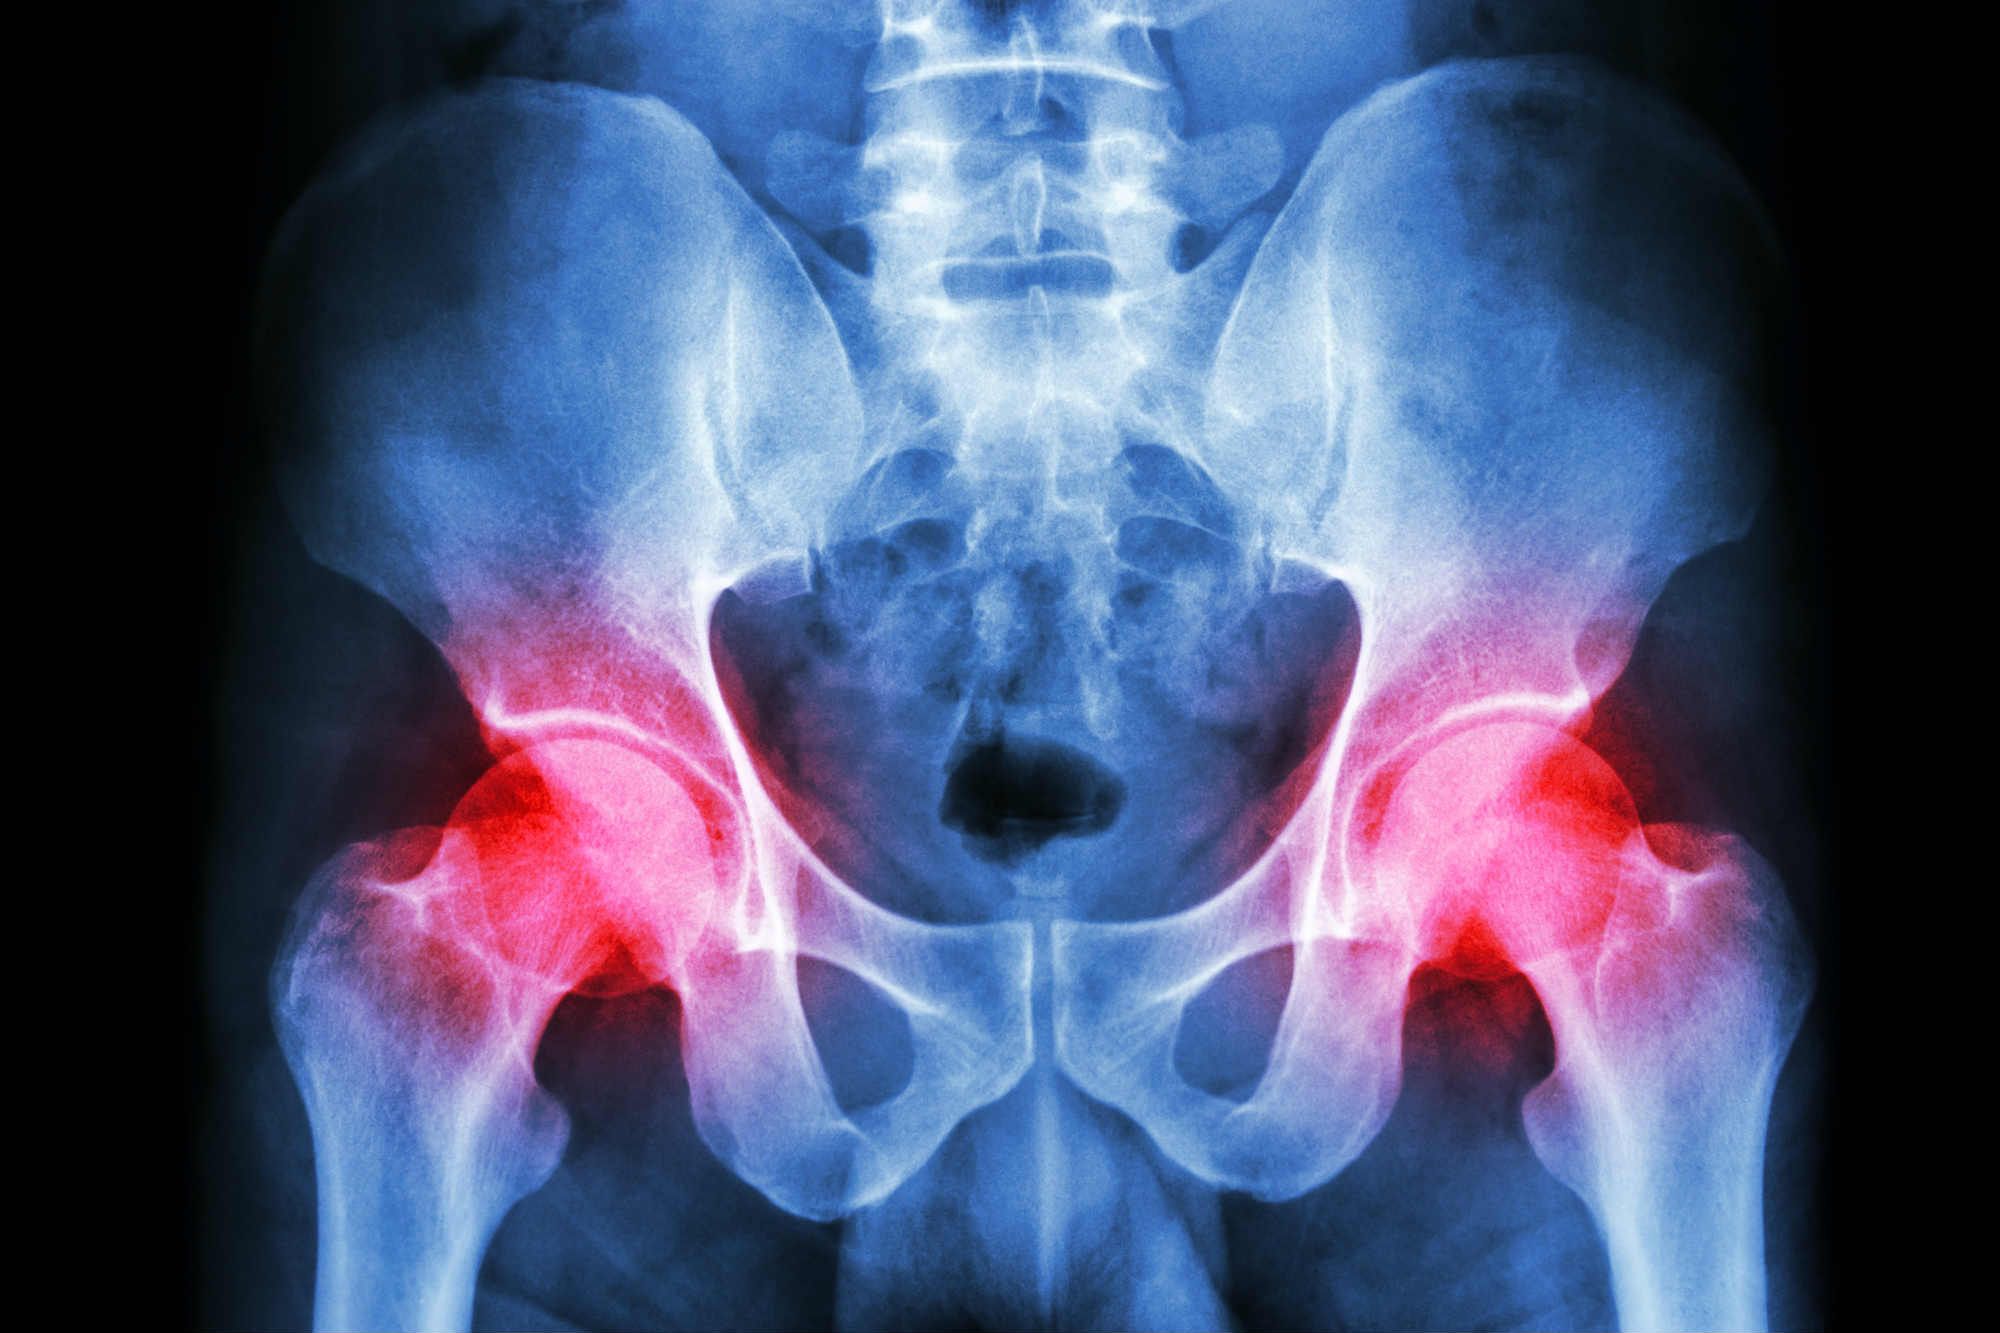

Zimmer Biomet Hip Replacement Lawsuit . Plaintiffs involved in the mdl have likely received their biomet hip replacement settlement. Zimmer biomet holdings has been sued over its faulty hip replacements in thousands of cases nationwide. Zimmer biomet hip replacement lawsuits claim the durom cup failed early, causing severe complications. There are currently 19 jury trials scheduled. The fda is getting the word out regarding a recall effort from zimmer biomet related to its discontinued cpt hip implant and. The defective medical device team of attorneys at weitz & luxenberg is inviting anyone who suffered a thigh fracture due to the. Mctlaw attorneys represent clients in lawsuits against zimmer biomet's metal on metal hip replacements. In july 2024, zimmer biomet issued a recall of their cpt hip system femoral stem 12/14 neck taper over concerns about the.

In july 2024, zimmer biomet issued a recall of their cpt hip system femoral stem 12/14 neck taper over concerns about the. Plaintiffs involved in the mdl have likely received their biomet hip replacement settlement. The defective medical device team of attorneys at weitz & luxenberg is inviting anyone who suffered a thigh fracture due to the. There are currently 19 jury trials scheduled. Mctlaw attorneys represent clients in lawsuits against zimmer biomet's metal on metal hip replacements. Zimmer biomet hip replacement lawsuits claim the durom cup failed early, causing severe complications. Zimmer biomet holdings has been sued over its faulty hip replacements in thousands of cases nationwide. The fda is getting the word out regarding a recall effort from zimmer biomet related to its discontinued cpt hip implant and.

Zimmer Biomet Hip Replacement Lawsuit There are currently 19 jury trials scheduled. Mctlaw attorneys represent clients in lawsuits against zimmer biomet's metal on metal hip replacements. Zimmer biomet holdings has been sued over its faulty hip replacements in thousands of cases nationwide. The defective medical device team of attorneys at weitz & luxenberg is inviting anyone who suffered a thigh fracture due to the. Plaintiffs involved in the mdl have likely received their biomet hip replacement settlement. Zimmer biomet hip replacement lawsuits claim the durom cup failed early, causing severe complications. There are currently 19 jury trials scheduled. In july 2024, zimmer biomet issued a recall of their cpt hip system femoral stem 12/14 neck taper over concerns about the. The fda is getting the word out regarding a recall effort from zimmer biomet related to its discontinued cpt hip implant and.